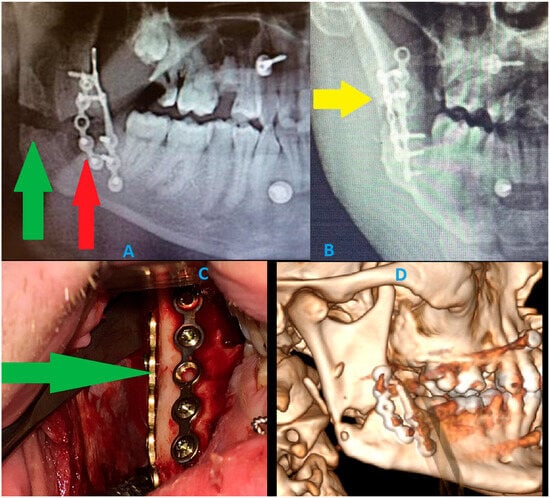

Figure 7. A panoramic radiograph has many limitations. Detecting the presence of a fracture is the first concern; however, a second important aspect is the limited ability to evaluate postoperative fracture healing, bone positioning, and overall stability. These images describe how cortical bone loss can impact the visibility of proper bone relations and their stable outcomes after surgery. These DPG limitations show how intraoperative proper bone reposition and osteosynthesis principles might be misdiagnosed in a routine radiograph [14,15]. A graphical story of the events is shown: (A) postoperative routine DPG. The osteosynthesis of both mandibular left basis and right mandibular angle fractures was stabilized (ORIF) with Medartis 2.0 Modus Mandible plating and screw systems (Medartis, Basel, Switzerland) and 4 IMF (intermaxillary fixation 2.0 SpeedTip self-drilling screws 11–14 mm long; Medartis, Basel, Switzerland). Rigid plating systems were used to ensure a good balance between load-bearing and load-sharing forces, related to the forces of the bite, occlusion, and attachment of the masticatory muscles. An additional steel wire was placed in the area of two teeth 34/35 as a Risdon wiring technique to additionally support the fracture line and maintain good occlusion. This control panoramic radiograph (A) shows a very good final result and occlusion; however, a large radiolucent area is noticeable at the right mandibular angle. This radiological appearance might suggest bone displacement or mandibular misalignment and a lack of proper reduction. Regarding the bone gap in the right mandibular angle, regardless of the proper condylar head position in the glenoid fossa and proper occlusion, and despite good intraoperative results, the findings were worrisome and might suggest a rotation of two bony fragments, lacking adequate bone contacts for healing, and might require secondary surgery to establish more accurate bone position and angulation. Each clinician should remember that panoramic radiographs (DPGs) have many limitations and should be evaluated with caution [2,3,4,5]. The green arrow points to the bone gap caused by the loss of buccal cortical bone after reposition, while the red arrow points to the loss of buccal cortical bone caused by the removal of impacted wisdom teeth and simultaneous wound debridement. These images (red and green arrows) were suspected to be a bone gap and an inappropriate final surgery result. (B) The additional A-P radiograph (anterior–posterior) half mandible projection suggests two bone fragment malalignments, with the occurrence of a radiolucent area suggesting some missing bone fragments (yellow arrow points on a slight crack and bone loss). Because panoramic radiographs are cheap, fast, and easy to make, many surgical results from surgery are not evaluated in postoperative CT scans as often. DPGs could lead to many false diagnoses and misinterpretations of the images; therefore, their usage should be limited. Most commonly, the bone fragment rotations are not noticeable on DPGs; the fracture line can be missed, as well as tilting of some bone fragments can occur. (C) The intraoral photograph shows a very good, stable outcome from bone stable reposition and osteosynthesis. Intraoperatively, good bone alignment and bone fragments were achieved. The loosened parts of the bone were removed to improve the repositioning outcome. The loss of some lingual cortical parts of the bone did not affect the repositioning. The green arrow points to a very good fracture reduction line. (D) Because the panoramic radiograph was inconclusive and suggested bone malalignment and displacement with bone fragments rotation, which suggested an indication for a secondary revision surgery, a postoperative CT was scheduled. The DPG suggested inappropriate surgery results, which were related to the removal of loosened bone fragments and the necessity to remove all small bone fragments from the fracture line, as well as the missing cortical parts of the bone. The CT examination revealed very good bone contact in the posterior and anterior aspects of the ascending ramus and the posterior part of the mandibular ramus. Despite the missing portion of buccal cortical bone from the ramus, the alignment of bone fragments was satisfactory, with no necessity for any secondary surgery. CT should currently be considered the gold standard for pre- and post-surgery bone evaluation; however, some authors do advise a low-dose CT protocol [3]. In cases of severe trauma, each surgeon has to carefully evaluate each mandibular and craniofacial skeleton trauma to plan the scope and stages of each surgery to restore good facial shape, size, and proper bone alignment. Since the first osteosynthesis methods were described and presented by Champy more than 40 years ago, the proposed protocol for mandibular stable osteosynthesis (ORIF) has continued to be used worldwide [3,5]. Classic routine panoramic radiographs should be evaluated carefully, and a certain degree of inaccuracy may be troublesome for interpretation. CT or low-dose CT should be considered as a more valuable and predictable diagnostic tool in mandibular trauma. From a radiological perspective, a careful DPG evaluation should always be improved with other radiological studies. To summarize, prophylactic miniplate osteosynthesis (PMP) as a preventive measure for the removal of impacted teeth or the removal of any mandibular lesions should be considered on an individual basis. A typical bone plating osteosynthesis used in common mandibular trauma cases, on the other hand, shares certain similarities and differences. One major aspect reveals a major limitation in DPG usage in all presented cases, where the full scope of bone fracture and its boundaries are not always easy to establish. Secondly, when a three-dimensional bone defect shape, volume, and boundaries cannot be evaluated, then some uneventful outcomes may occur for the patient after a mandible lesion surgery (example: impacted teeth, cyst, and tumor removal). Those situations might include bone mobility, bending, instability, or a fracture that might occur sometime after the initial procedure. PMP, with either plates of IMF, offers a better prognosis and enables good healing and bone stability, especially when combined with additional bone grafting materials (xenograft, allograft, and autologous bone) to improve bone volume during the same procedure focused on a specific mandibular lesion [16,17]. DPG has many limitations in fracture evaluation; however, PMP could have a great impact, specifically decreasing pathological fractures of the mandible after some mandibular lesion surgeries. Key Radiologic Teaching Message: The presented cases illustrate that panoramic radiography and even CBCT may underestimate the true biomechanical vulnerability of the mandible when large cystic defects cause extensive cortical thinning without an obvious fracture line. A well-defined unilocular pericoronal radiolucency with marked buccolingual expansion and near-complete attenuation of the inferior cortex should be interpreted as a fracture-prone configuration, even if standard radiology appears “borderline” or inconclusive. In such situations, radiologists and surgeons should explicitly report the degree of cortical thinning and consider the mandible at high risk for delayed pathological fracture, thereby prompting discussion of prophylactic mandibular plating or, at a minimum, strict postoperative protection and close radiologic follow-up.